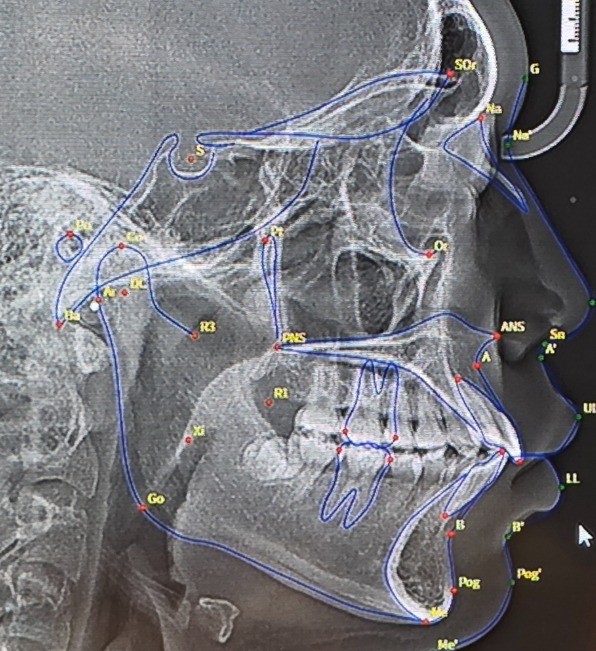

Upload the ceph x ray without the analysis on top and I'll do you an actual cephalometric analysis (for free) because this isn't professional at all. What it looks like though is that you have a skeletal class II deep bite, an MSE with a facemask wouldn't help.

i plan on getting mse + facemask, after my maxilla comes forward i would have to use braces to bring the teeth back but slightly recess the maxilla, right?